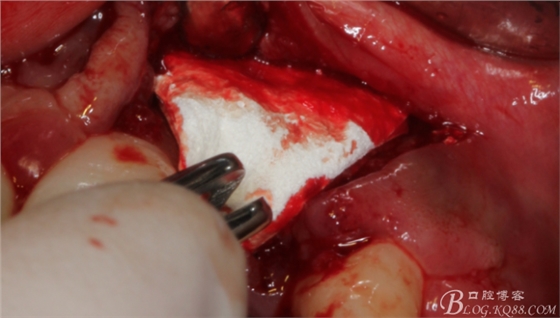

于是我果斷告知患者,手術(shù)失敗了,不能拖延,如不及時(shí)處理,炎癥繼續(xù)發(fā)展會(huì)很快波及鄰牙牙槽骨。患者接受我的建議。切開翻瓣,骨粉及生物膜消失了,骨吸收嚴(yán)重,幸運(yùn)的是,因?yàn)樘幚砑皶r(shí),鄰牙骨支持依然存在。

徹底掻刮。